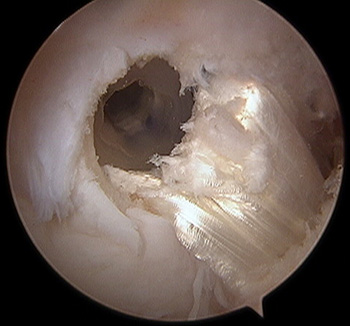

maestu1_fig8

Figura 8: vista artroscópica desde portal anterolateral en una rodilla derecha de guía de tornillo para fijación banda posteromedial.